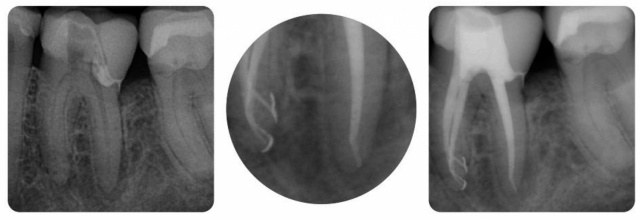

ausreichend auf voller Länge mit EDTA und NaOCl gespült. Dann werden Seitenkanäle eröffnet und darin

befindliche Gewebereste aufgelöst. Eine gute Spülung ist daher nach geeigneter thermoplastischer Wurzelfüllung

auch im Röntgenbild sichtbar und ein Qualitätskriterium. Der Verlauf der Wurzelfüllung ist klar abgegrenzt

und Seitenkanäle sind durch die Wurzelfüllung mit erfasst.